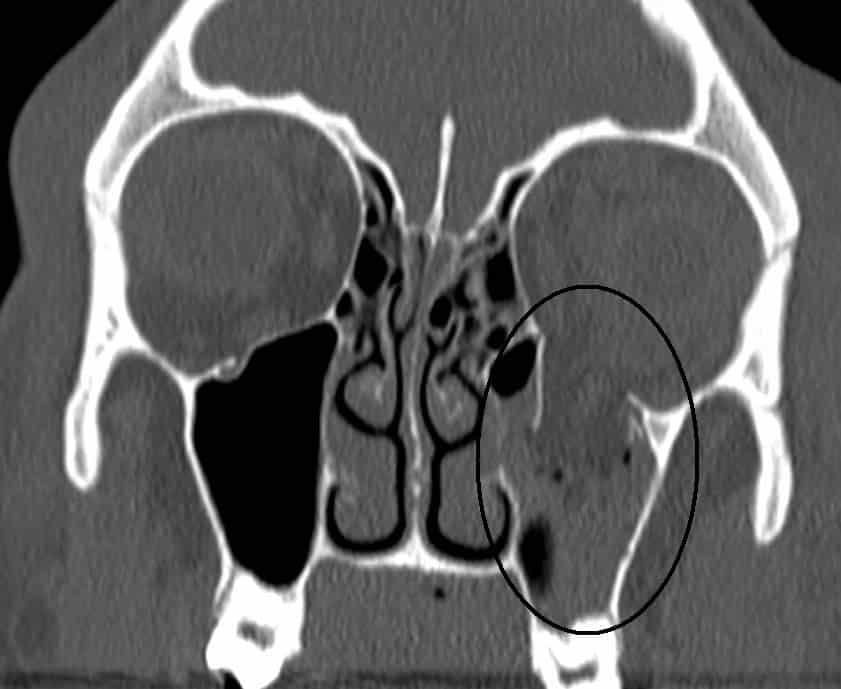

Fig 1.3 - CT scan of a blowout fracture of the eye, through the inferior wall. The contents of the orbit have herniated into the maxillary sinus.

CT scan of a blowout fracture of the eye, through the inferior wall. The contents of the orbit have herniated into the maxillary sinus.

• ‘Blowout’ fracture – This refers to partial herniation of the orbital contents through one of its walls. This usually occurs via blunt force trauma to the eye. The medial and inferior walls are the weakest, with the contents herniating into the ethmoid and maxillary sinuses respectively.

Any fracture of the orbit will result in intraorbital pressure, raising the pressure in the orbit, causing exophthalmos (protrusion of the eye). There may also be involvement of surrounding structures, – e.g haemorrhage into one of the neighbouring sinuses.